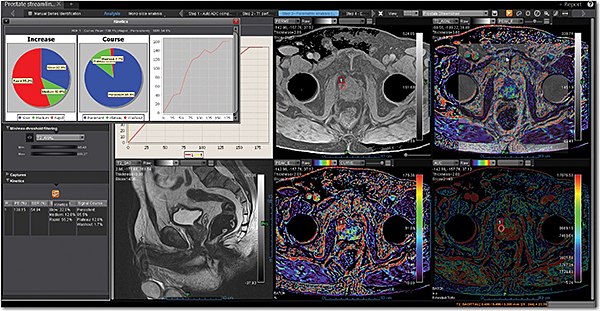

Додаток Prostate Streamlined.

Спеціальні програми Olea SphereTM для аналізу передміхурової залози включають в себе розширені можливості для оцінки дифузії та якісної оцінки перфузії. Також пропонують ефективний мультипараметричний аналіз усіх доступних послідовностей для візуалізації простати. В додатках реалізовано аналіз кінетики та кількісних даних на основі надійних математичних моделей. Програми передміхурової залози включають звіт PI-RADS® 2 для покращення виявлення, характеристики та вірогідності встановлення діагнозу раку простати. Цей програмний пакет стандартизує виклад протоколів опису, а також вказує рівень підозри або ризик виникнення клінічно значущих пухлин.

Додаток MR Prostate

Додаток MR Prostate інтегровано до розширеної візуалізації Vitrea. Він забезпечує виявлення, характеристику та стадіювання ураження.

Забезпечує миттєву комплексну оцінку ураження та високоякісну оцінку дифузії

Дає змістовну звітність, включаючи локалізацію та об’єм ураження

Надає рекомендації PI-RADS V2 щодо стандартизації термінології і протоколу опису, а також уточнює ризик клінічно значущих пухлин